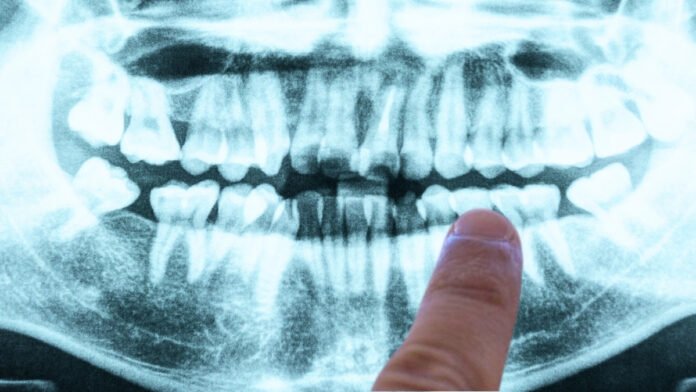

A 2019 study suggests that Alzheimer’s may be related to gum disease. According to the research, led by senior author Jan Potempa, a microbiologist from the University of Louisville, the presence of Porphyromonas gingivalis – the pathogen behind chronic periodontitis (or gum disease) – was found in the brains of deceased Alzheimer’s patients.